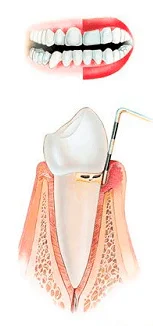

Стадии пародонтита

1 стадия |

2 стадия |

До недавнего времени в Омске использовали только очень болезненный способ лечения пародонтита с помощью уколов, теперь в нашей клинике применяется инновационный безболезненный подход к лечению десен с мощью лазера. Прочитать подробнее о лечении пародонтита с помощью лазера.

Стоимость лечения пародонтита около 5 000 ₽, конечная стоимость зависит от степени поражения. Пародонтит также как и чистку зубов необходимо делать регулярно (раз в пол года, максимум 1 раз в год), при этом лечение пародонтита стоит в 2 раза дороже!